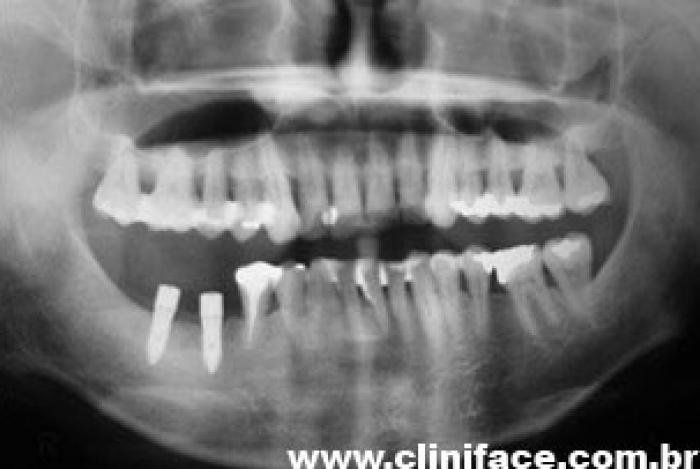

Raio X final